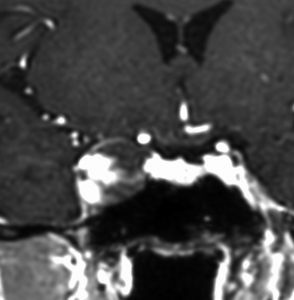

海綿静脈洞内海綿状血管腫

右外転神経麻痺で発症した血管腫です。一見,三叉神経鞘腫のように見えるのですが,ガドリニウム増強のパターンが違います。出血するので面倒ですが全摘出できるものです。